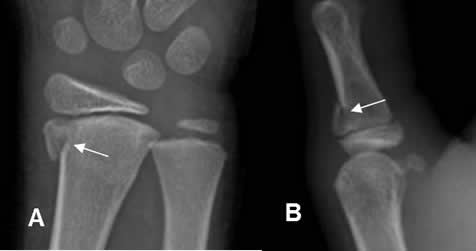

Fig 68 A. Salter tipo I.

A: Rx AP y B: Rx oblicua. Pérdida de la alineación entre la metafisis y la epifisis, por deslizamiento epifisiario tipo I.